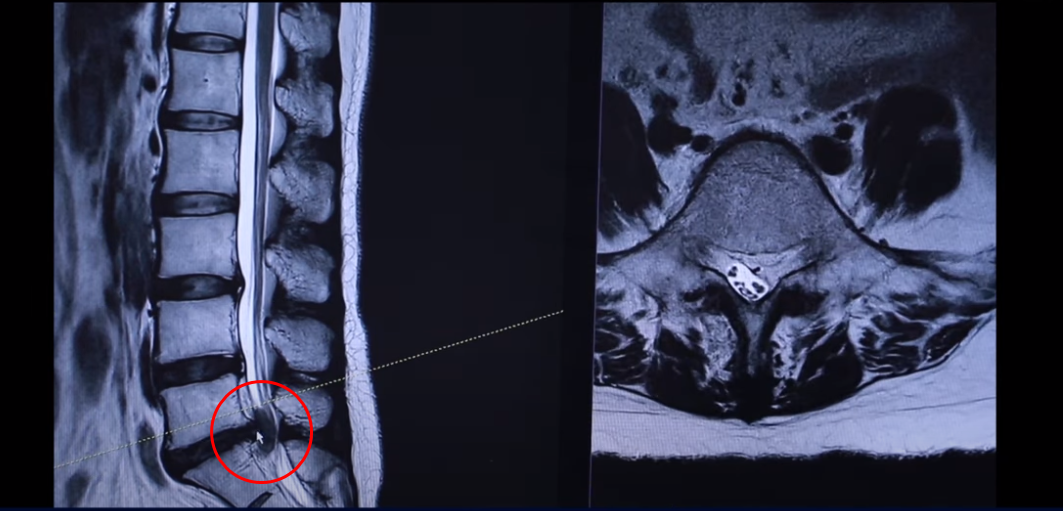

다시 동생분 MRI로 돌아가겠습니다. 언니분하고 똑같이 이 동생분 세 마디 디스크가 퇴행돼 있죠 그리고 마지막 마디가 터져서 이렇게 왼쪽으로 심하게 밀려 나가 있습니다.

언니분보다 터진 정도는 더 심합니다. 그래서 이렇게 디스크가 심하게 파열되고 또 마비 증상까지 있는 분들 이런 분들은 이 환자분이 들으신 것처럼 정형외과나 신경외과에서 즉시 수술을 해야 된다. 또 마비 증상까지 있으니까 바로 수술을 하지 않으면 마비 증상이 오래되면 신경이 심하게 눌려 있으면 신경 기능이 많이 떨어지면 만약 마비가 풀리지 않는다고 그러면 그건 이제 장애가 되는 거죠. 그렇기 때문에 즉시 수술을 해야 된다 이렇게 듣는데 이렇게 파열이 심한 분들일수록 저희는 오히려 비수술 재활 치료가 성공할 확률이 더 높다. 역설적이게도 파열이 심하면 심할수록 치료가 더 잘될 확률이 높다. 저희 모커리한방병원이 이렇게 설명을 하고 있는데 왜 그럴까요?

파열이 심하면 심할수록 오히려 비수술 치료가 더 잘 된다고 저희가 설명하는데 역설적이죠. 그렇게 얘기하는 이유는 뭐냐면 이렇게 심하게 파열된 디스크는 우리 몸에서 이물질로 인식하기 때문에 흡수가 매우 잘 됩니다. 그래서 이분이 치료가 끝난 뒤 6개월에서 1년 사이에 MRI를 다시 찍어보시면 밀려나와 있던 디스크 수핵이 흡수돼 있는 걸 보실 수 있습니다. 이렇게 심하게 튀어나온 디스크는 이물질로 인식되기 때문에 우리 몸에 면역 시스템에서 녹여서 없애버리는 겁니다. 이 안으로 흡수되는 게 아니죠. 녹아서 우리 몸에서 없어지는 겁니다. 그래서 파열이 심하면 심할수록 흡수가 더 잘 됩니다. 그게 첫 번째 이유고 치료가 잘 되는 두 번째 이유 이렇게 심하게 터진 분들은 거의 대부분 방사통이 너무너무 심해서 또 마비 증상까지 있기 때문에 일상생활이 불가능합니다. 일상생활이 불가능하니까 출근할 생각도 하지 않는 거죠. 나가서 일할 생각도 하지 않고 공부하는 학생이라면 공부할 생각도 하지 않습니다. 일단은 치료가 중요하죠. 그래서 일단 급하게 수술을 받든가 아니면 입원 치료를 하게 돼 있습니다.